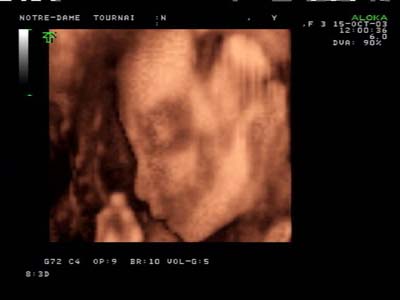

Analyse 3D : Echographie temps réel